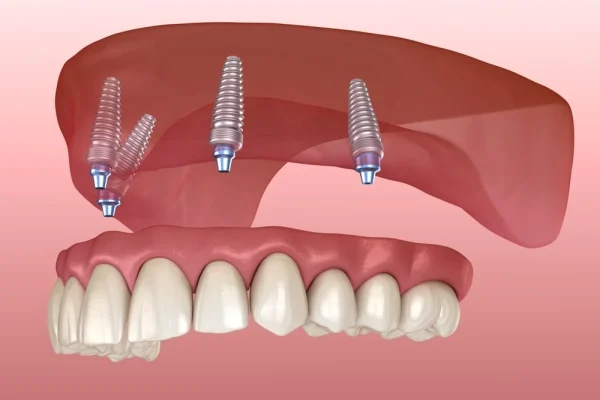

At Dentale Albania, we believe dental care abroad should be as stress-free as possible. That’s why we’re expanding our service offerings to include comprehensive travel packages that go beyond dentistry. From airport pickup and 4-star accommodation to local tours, our packages are crafted to give you not just a new smile — but an unforgettable Albanian experience. Whether you’re here for implants, veneers, or full-arch restorations, we handle everything so you can focus on your transformation.